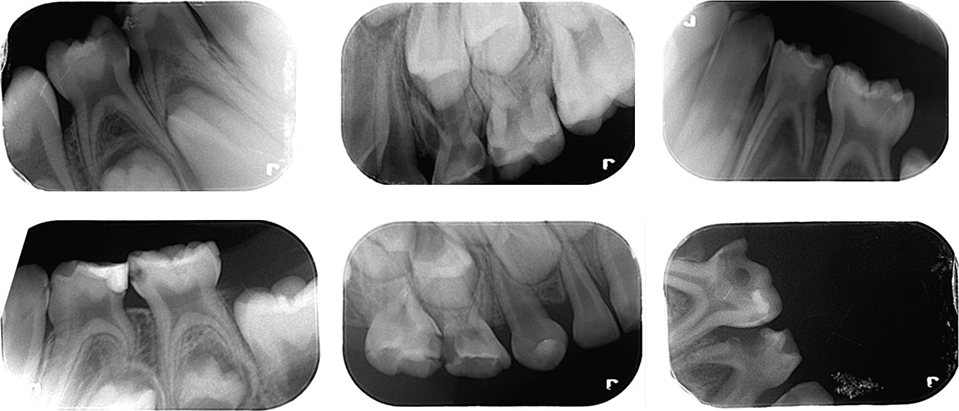

This work was approved by Tekirdag Namik Kemal University Ethics Committee (approval No. 2022.240.12.18) and carried out at the Department of Pediatric Dentistry, Faculty of Dentistry Tekirdağ Namık Kemal University, Turkey. To detect approximal caries in children, a unique dataset was created by collecting periapical radiographic images. All radiographs with aproximal lesions, excluding unclear ones, were included in the study. Only non-clear radiographs were excluded from the dataset. Hence, a unique dataset of periapical radiographs was obtained. Some of these radiographic images are given in Figure 1.

Figure 1. Some of the collected radiographic images.